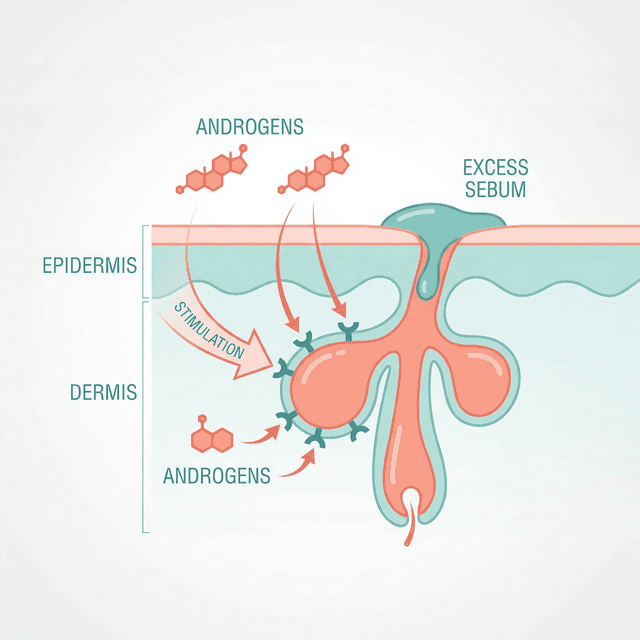

Testosterone and Acne: Why Hormones Drive Most Teen Breakouts

Testosterone gets converted to DHT, which ramps up your oil glands. This is the core reason acne peaks during puberty and why boys tend to get it worse than girls.

Hormonal Acne in Teenagers: Why It Happens and What Actually Works

Hormonal acne affects nearly every teenager, but understanding why it happens gives you a real advantage. Here's how puberty triggers breakouts and what treatments dermatologists actually recommend.